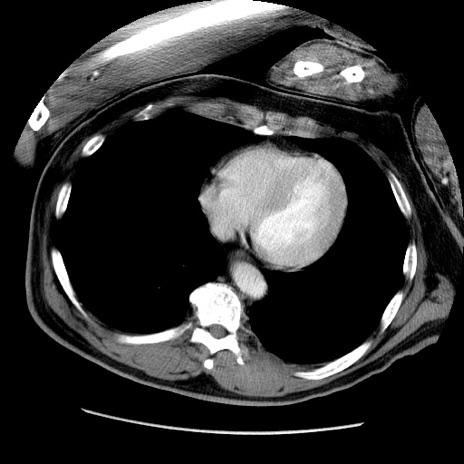

冠状断像